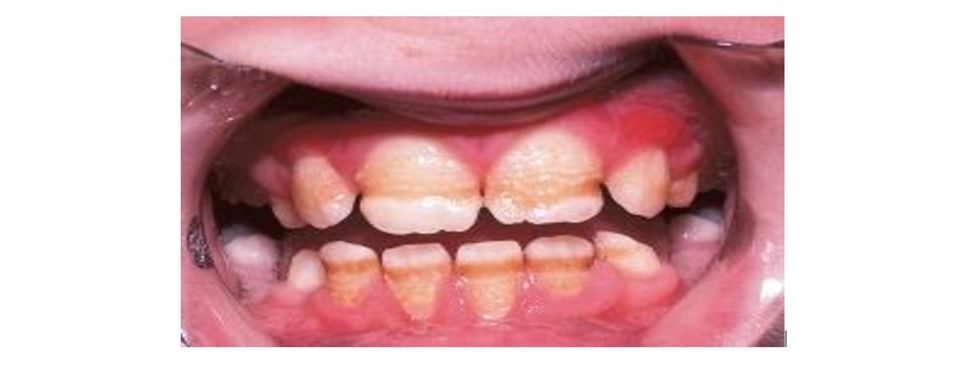

Mungesa e vitaminës D shkakton demineralizim të strukturës së dhëmbëve, gjë që mundëson terren të përshtatshëm për zhvillimin e kariesit të dhëmbëve (prishjes së dhëmbëve).

Mungesa e vitaminës D, përveç çrregullimeve të përgjithshme që shkakton në organizmin e njeriut, ajo mund të na sjellë edhe deri tek shumë ndryshime në hapësirën orale.

Simptomat që shfaqen në hapësirën orale nga mungesa e vitaminës D janë:

▪ Kariesi apo prishja e dhëmbëve ndodh brenda një afati kohor shumë të shpejtë dhe të shkurtër, ku struktura e dhëmbëve është e brishtë dhe e demineralizuar.

▪ Dhëmbët kanë strukturë të dobët, që thyhen lehtësisht apo krijohet derdhje e strukturës së tyre, e cila pastaj është teren i përshtatshëm për retencion dhe atakim nga kariesi dhe sëmundjet gingivale e parodontale (sëmundjet e mishrave dhe shtratit të dhëmbit).